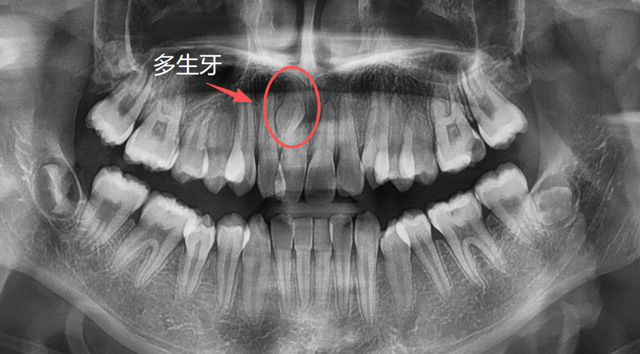

儿童上颌多生牙

建议家长在小朋友处于替牙期的时候,不管有没有牙疼,都找专业的口腔医生进行检查,必要时拍片看一下牙胚的数量有无出入,关注一下牙齿是否按正常的顺序完成了替换,如有异常情况,可以及时干预。

牙根的形态、数量是天生的,无法后天干预,但是对于部分异位牙、埋伏牙,我们可以在小朋友替牙期的这个阶段通过相应的医学手段来干预,避免一些成年后的拔牙。